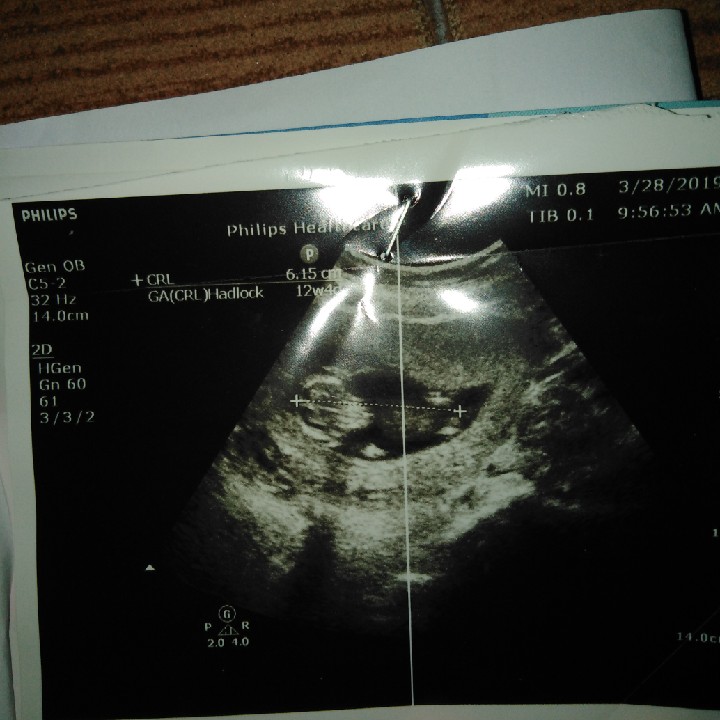

12w4dค่ะ